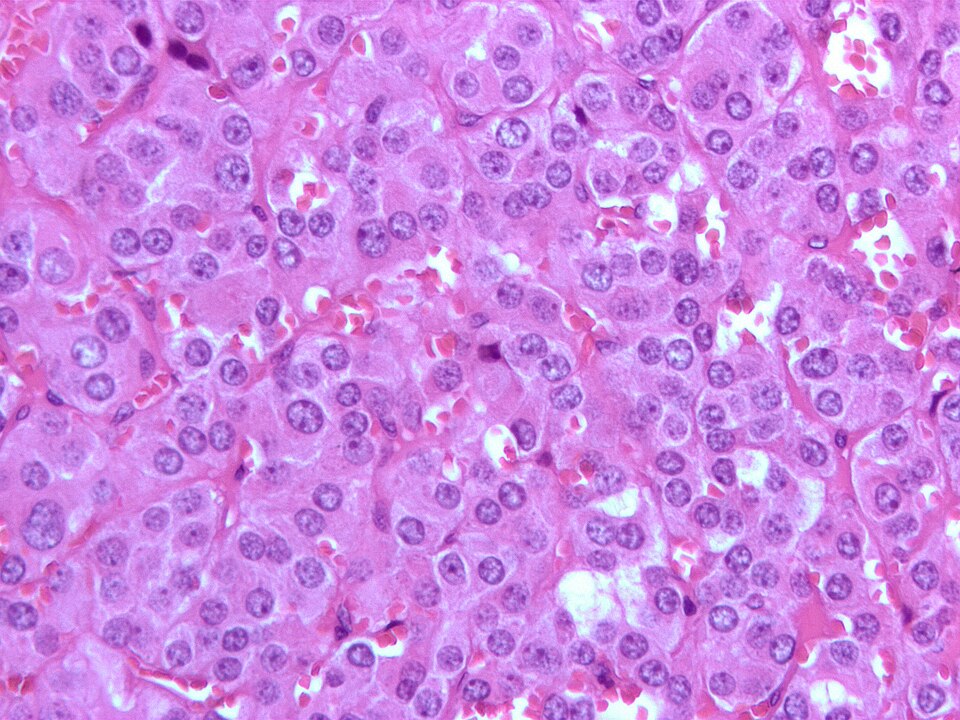

Feochromocytom je zajímavý typ nádoru nadledvin, který vychází z jejich dřeně. Většinou je nezhoubný (někdy však může být i zhoubný a vytvářet metastázy), ale přesto může ohrožovat nemocného na životě.

Feochromocytomy jsou vzácné neuroendokrinní nádory s velmi proměnlivými klinickými projevy, pro nějž jsou typické záchvatovité obtíže – bolesti hlavy, pocení, palpitace a hypertenze.

Feochromocytom je nádor z chromafinních buněk produkujících katecholaminy, které vyvolávají hypertenzi. Katecholaminy, které produkuje feochromocytom způsobují buď trvalou hypertenzi (vysoký krevní tlak), popřípadě epizody nebo záchvaty vážné hypertenze. Dalšími příznaky nadměrné produkce katecholaminů jsou bolesti hlavy, bušení srdce, pocení, nevolnost, úzkost a… Wikipedie